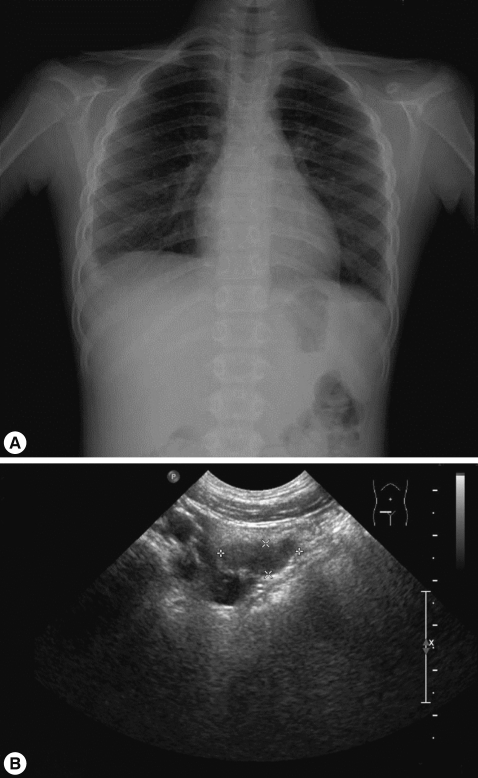

On admission, her vital signs were as follows: body temperature, 37.8℃; heart rate, 90/min; respiratory rate, 24/min; and blood pressure, 100/70 mmHg. On examination, she looked very ill and her breathing sounds were decreased on both sides of the lower chest. Moderate tenderness was detected in the right flank and the right inguinal area. A chest radiograph indicated pleural effusion (Fig. 1), and abdominal sonography revealed an inflammatory lesion in the right psoas muscle (Fig. 2). Her total white blood cell (WBC) count was 26,900 cells/mm3, hemoglobin level was 10.7 g/dl, erythrocyte sedimentation rate (ESR) was 75 mm/hr, and C-reactive protein concentration was 71 mg/dl. The patient also presented with hypereosinophilia (66%), and the total serum IgE value higher than 2,500 IU/ml. Because her dietary history and laboratory findings were indicative of a parasitic infection, we performed a serum antibody test using ELISA and examined her stool, sputum, and pleural fluid specimens [11]. No evidence of parasite eggs in the stool or sputum specimen was obtained, but ELISA was positive for P. westermani in the serum, with an optical density (OD) of 0.619 (cut-off OD: 0.255). The pleural fluid obtained by thoracentesis revealed the following findings: WBC, 26,200 cells/mm3 (neutrophils, 25%; lymphocytes, 72%); pH, 7.129; proteins, 8.2 g/dl; albumin, 2.1 g/dl; glucose, 5 mg/dl; and turbid appearance. Gram staining, culture studies, and tuberculosis- PCR (TB-PCR) in the pleural fluid, however, were negative.

Praziquantel therapy was initiated at a dose of 25 mg/kg, 3 times a day for 2 days. Two days after admission, fever subsided, the pleural effusion decreased, the abdominal pain improved, and the follow-up chest radiograph showed improvement. On the 6th day of hospitalization, she was discharged. However, at the next follow-up visit, her peripheral blood was still positive for hypereosinophilia (74.9%); therefore, an additional cycle of praziquantel therapy was recommended.

One month after the first admission, the eosinophil count in the peripheral blood and the total serum IgE value were still high (eosinophils, 37.4%; IgE, 1,094 IU/ml). The follow-up chest radiograph showed improvements of the left pleural effusion, but persistence of the right pleural effusion (Fig. 3A). She was, therefore, readmitted to the hospital, and the pleural fluid was drained using a pigtail catheter.

The major symptoms of paragonimiasis are cough, hemoptysis, and dyspnea; some of these overlap with symptoms of tuberculosis and other pulmonary disorders. Pulmonary infiltrates, effusion, nodules, or lesions are also very common [14, 15], and ectopic locations of flukes include the pleura, abdominal wall, viscera, and brain. In our case, the patient complained of abdominal pain, especially in the right flank and right inguinal area but had no cough, dyspnea, or chest pain. The chest radiograph revealed pleural effusion, and abdominal sonography showed a low-echoic lesion with inflammation of the surrounding fat in the psoas mucle. This lesion is presumed to be due to adult flukes, which are present in loosely formed cysts in the psoas muscle.